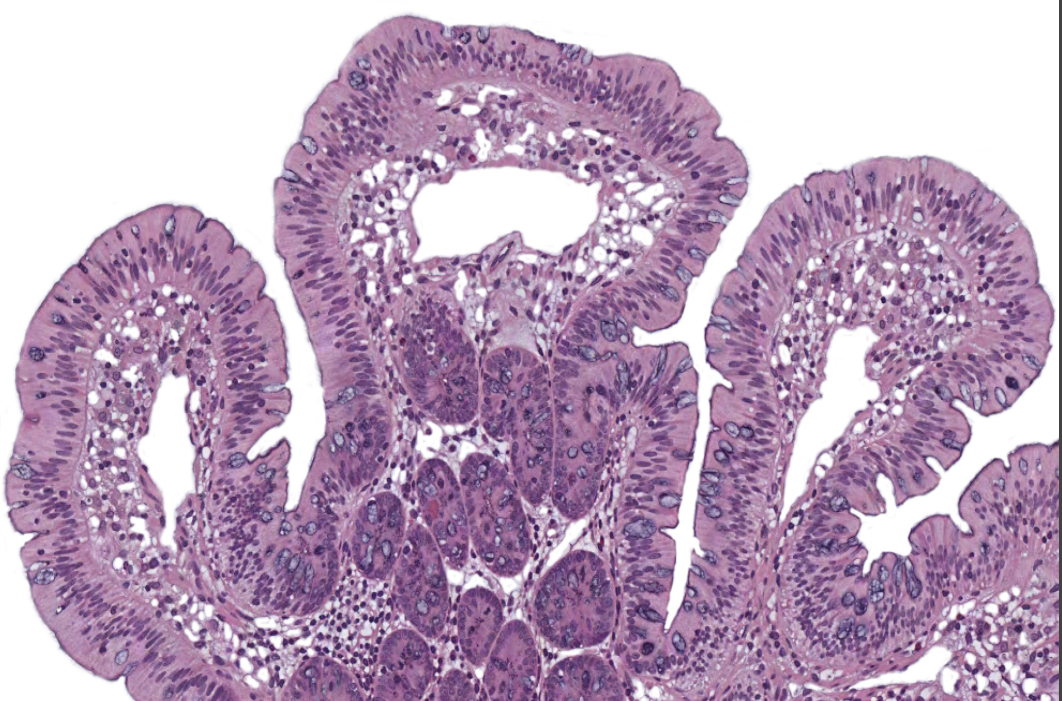

Small Intestine

NOTICE: THE FINGER-LIKE PROJECTIONS (VILLI) WITH OPEN SPACE INSIDE AND A FEW GRAY/BLUE GOBLET CELLS ALONG THE SIDES (NOT AS MANY AS LARGE INTESTINE